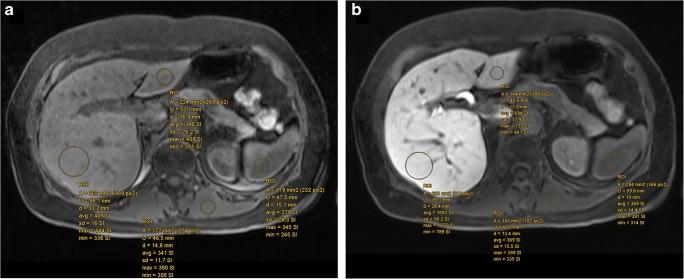

To examine inter- and intra-observer agreement for four simple hepatobiliary phase (HBP)-based scores on gadoxetic acid (GA)-enhanced MRI and their correlation with liver function in patients with mixed chronic liver disease (CLD).

This single-center, retrospective study included 287 patients (62% male, 38% female, mean age 53.5 ± 13.7 years) with mixed CLD (20.9% hepatitis C, 19.2% alcoholic liver disease, 8% hepatitis B) who underwent GA-enhanced MRI of the liver for clinical care between 2010 and 2015. Relative liver enhancement (RLE), contrast uptake index (CUI), hepatic uptake index (HUI), and liver-to-spleen contrast index (LSI) were calculated by two radiologists independently using unenhanced and GA-enhanced HPB (obtained 20 min after GA administration) images; 50 patients selected at random were reviewed twice by one reader to assess intra-observer reliability. Agreement was assessed by intraclass correlation coefficient (ICC). The albumin-bilirubin (ALBI) score, the model of end-stage liver disease (MELD), and the Child-Turcotte-Pugh (CTP) score were calculated as standards of reference for hepatic function.

Intra-observer ICCs ranged from 0.814 (0.668-0.896) for CUI to 0.969 (0.945-0.983) for RLE. Inter-observer ICCs ranged from 0.777 (0.605-0.874) for HUI to 0.979 (0.963-0.988) for RLE. All HBP-based scores correlated significantly (all p < 0.001) with the ALBI, MELD, and CTP scores and were able to discriminate patients with a MELD score ≥ 15 versus ≤ 14, with area under the curve values ranging from 0.760 for RLE to 0.782 for HUI.